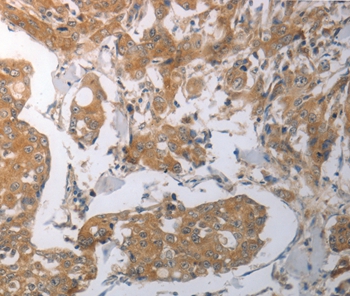

Immunohistochemical analysis of paraffin-embedded Human breast cancer tissue using #37028 at dilution 1/70.

Immunohistochemical analysis of paraffin-embedded Human colon cancer tissue using #37028 at dilution 1/70.